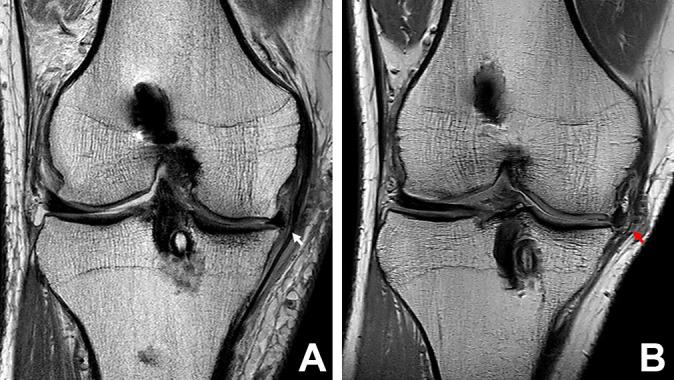

A total of 30 patients who underwent MMAT between December 1996 and March 2016 were enrolled. Allograft extrusion was measured on magnetic resonance imaging scans obtained at 6 weeks, 1 year, and 3 to 7 years postoperatively. In the coronal plane, the absolute allograft extrusion and relative percentage of extrusion were measured. In the sagittal plane, the absolute and relative anterior cartilage meniscal distance and posterior cartilage meniscal distance were measured. The joint-space width (JSW) on radiographic Rosenberg view was measured at 3 time points. The axial alignment was measured preoperatively and at the midterm follow-up.

In the coronal plane, there were no significant differences in absolute and relative coronal extrusions between 6 weeks and 1 year postoperatively; however, the values were significantly increased at midterm follow-up compared with both of the earlier follow-up periods. Similarly, in the sagittal plane, the mean absolute and relative anterior and posterior cartilage meniscal distances were not significantly different between 6 weeks and 1 year postoperatively but showed significant increases at midterm follow-up compared with both of the earlier follow-up periods. The mean preoperative axial alignment showed a positive correlation with the delta value of relative percentage of extrusion in the coronal plane ( = 0.378; = .036). The mean JSW was 4.42 ± 0.88 mm preoperatively, 4.30 ± 0.83 mm at 1-year follow-up, and 3.96 ± 1.06 mm at the midterm follow-up. No significant difference was found between the preoperative and postoperative 1-year values, but the mean JSW was significantly decreased at midterm follow-up compared with both of the other time points ( = .001 for both).

Allograft extrusion did not progress until 1 year after MMAT; however, by midterm follow-up, extrusion had progressed in both the coronal and the sagittal planes. Preoperative axial alignment showed a positive correlation with allograft extrusion in the coronal plane.